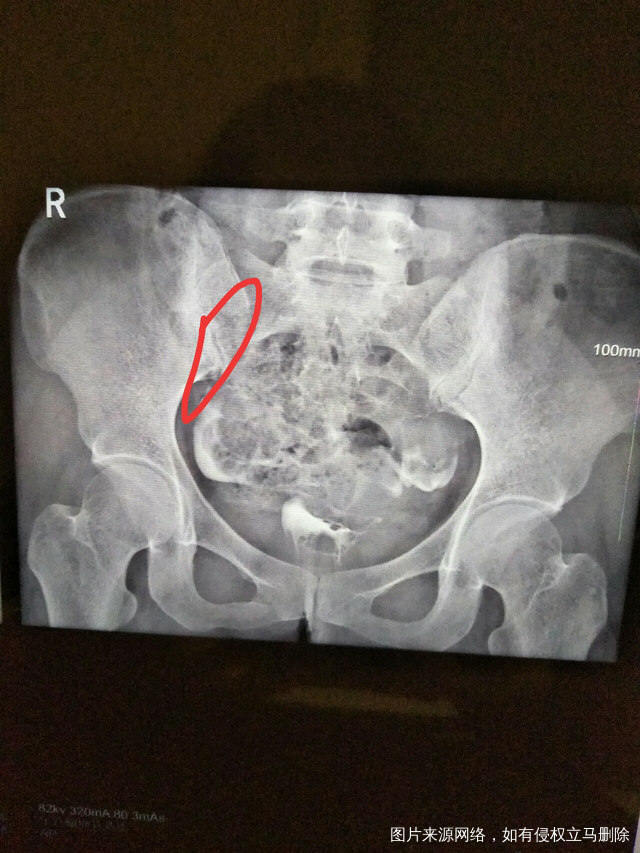

求助帮忙看看造影片子

做完输卵管造影第六天了小腹还是感觉沉甸甸的如

可以热敷腹部,如果有发热,腹痛加剧,白带量多,有异味,随时就医